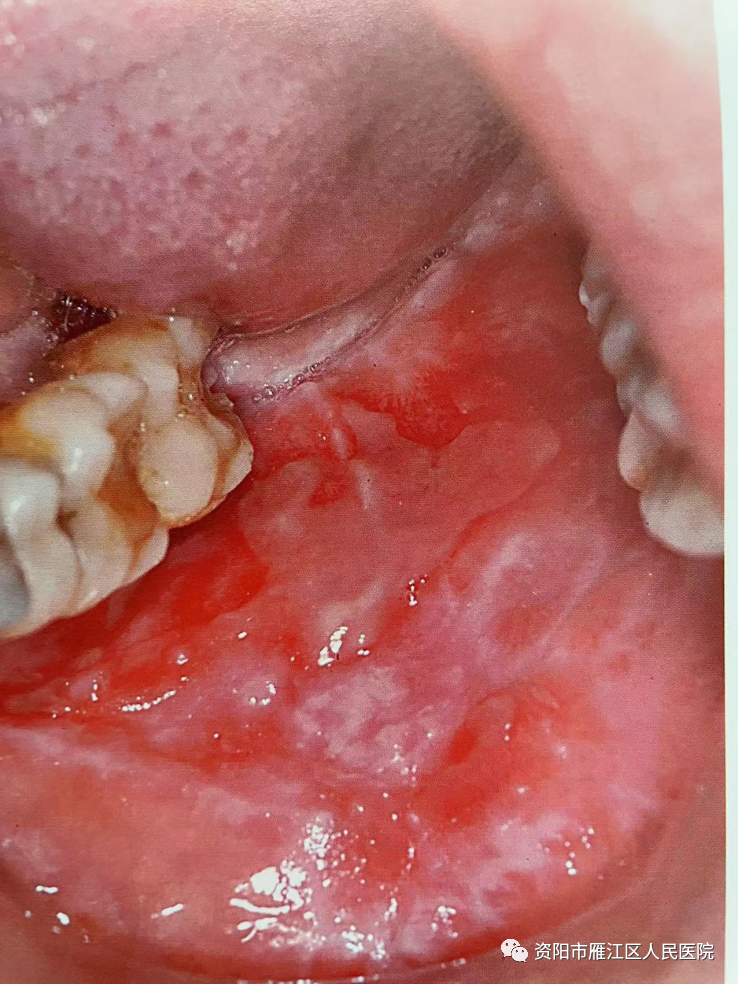

近日,刘先生经人介绍来到我院口腔科就诊。“大夫,我嘴巴里面长溃疡了,反反复复,可咋办?”经详细询问病史及系统性的临床检查,发现刘先生口腔两侧颊部粘膜广泛糜烂面,周缘树枝状白色条纹,临床诊断为“口腔扁平苔藓”。

口腔扁平苔藓是口腔最常见的疾病之一,是一种慢性炎症性疾病。好发于女性,一般在30-60岁之间,患病率约0.5%~3%。主要表现为双颊、牙龈、舌头等黏膜上的网状、环状、树枝样白纹,也有患者表现为白色斑块状,可伴黏膜充血、糜烂,进食辛辣刺激或较烫的食物时出现疼痛,有少数患者同时伴有皮肤病损。